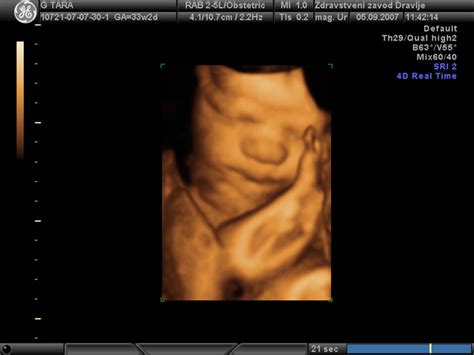

- 10.-14. teden: Opravi se ultrazvočna preiskava preko trebuha, s katero se oceni zgodnji razvoj ploda, tveganje za Downov sindrom in druge kromosomske nepravilnosti. Na željo nosečnice je možno opazovanje ploda s 3D/4D prikazom. Odvzamemo kri za dvojni hormonski test (DHT), ki skupaj z ultrazvočno oceno doseže zanesljivost okoli 90%. V tem obdobju je na voljo tudi naprednejši NIPT test (neinvazivni presejalni test) z 99,3% zanesljivostjo za določanje Downovega sindroma in drugih pogostih kromosomskih nepravilnosti. Ta test je neinvaziven in varen za plod, saj zahteva le eno epruveto krvi nosečnice.